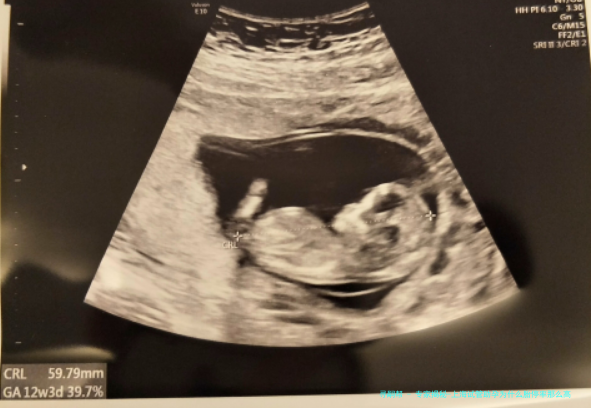

试管助孕家庭常将胚胎移植当成“尽头”,竟不知妊娠初期如在悬崖边行走。喜悦之后,忽然的胎停育让众多家庭措手不及——超声检查时那本该搏动的心跳,只剩余凝结的缄默。上海好些家生殖NF中心观察到,试管妊娠成功后约八周左右是胚胎停止发育的集中发生期。为何当代医药学技术将胚胎递入子宫后,仍难逃这一结局?细致分析后,免疫系统的异样反应正成为松开谜题的重点头绪。